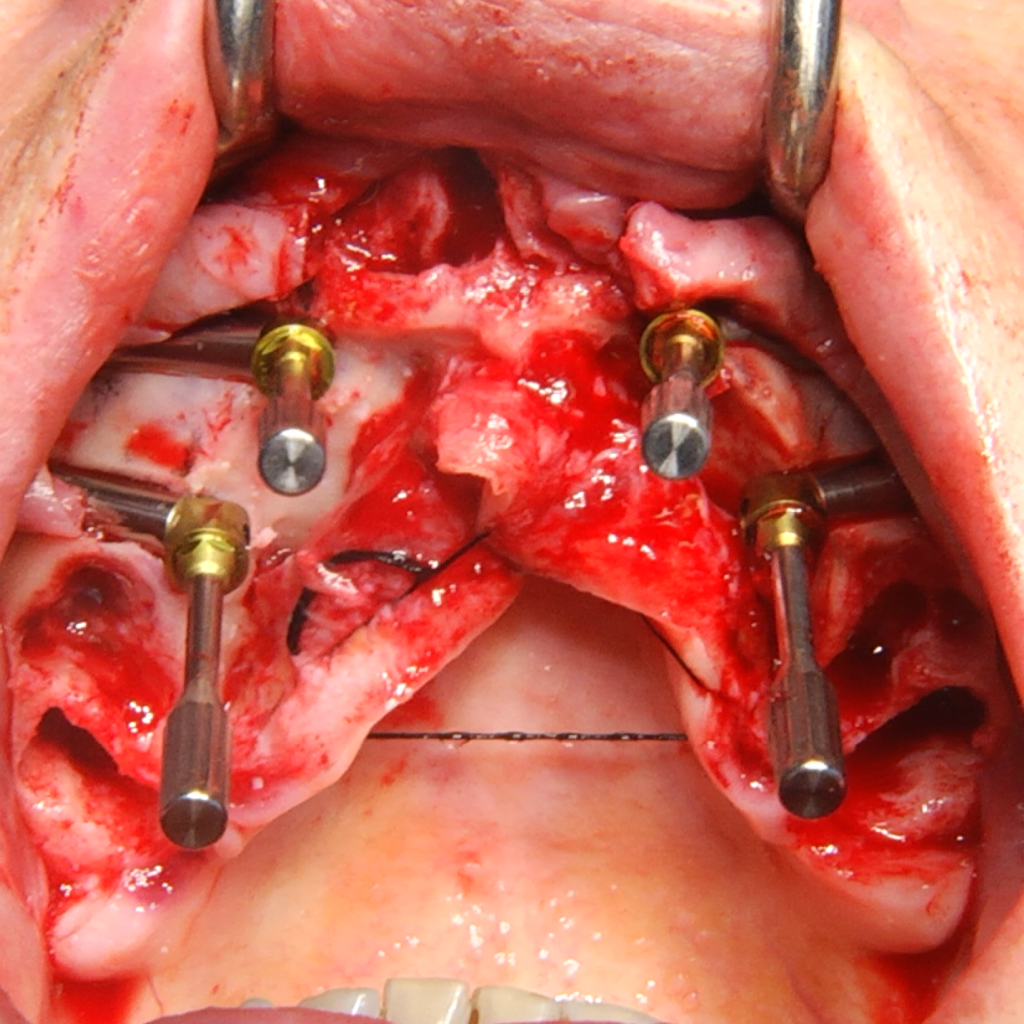

Extra alveolar anchorage sites for the rehabilitation of severe maxillary atrophy

This book by Dr. Tommaso Grandi presents an advanced protocol for the treatment of maxillary atrophy using Pterygoid, Trans-Sinus, Trans-Nasal and Zygomatic implants.

Clinical cases for each type of implant

20 Clinical cases performed by Dr. Grandi classified by type of treatment